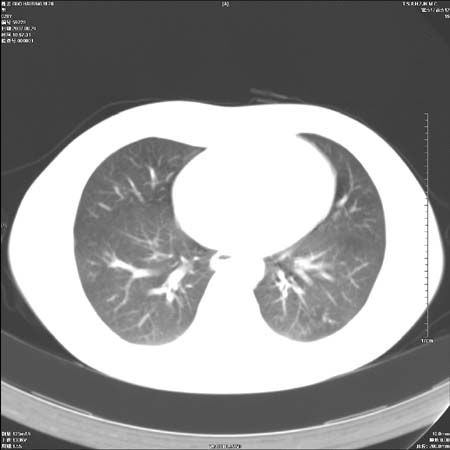

男性,28岁,体检发现左肺病变,患者只有背部隐痛感,哀哉,真不忍心下诊断啊。

左肺门区软组织肿块,左肺上叶支气管开口消失,纵隔内见肿大淋巴结,考虑左中心型肺部,可以做纤支镜取病理确认.

左肺肺门区肿块影,分叶明显:诊断肺癌应该没有疑问。

本例倾向周围型肺癌

鉴别:中央型肺癌-肿块那么明显一般合并节段肺不张或阻塞性炎症。

本例肿块边缘外侧可见左上叶各段支气管。

肺癌可能性大。(有分叶,毛刺)

左肺肺门区肿块影,分叶明显,左肺上叶支气管开口受压,纵隔内见肿大淋巴结,考虑左中心型肺癌。

左侧肺门区见一块状病灶可见分叶,纵隔内及左肺门见肿大淋巴结,应该是周围型肺癌而不是中心型肺癌,原因有以下2点,1未见阻塞肺气肿和阻塞性炎症,这么大肿块如果是中心型肺癌就是未分化型或小细胞型肺癌不出现阻塞性肺不张也应该有阻塞炎症或阻塞性肺气肿,2如果是中心型肺癌临床出现最早的症状是咳嗽(此时可无任何异常影象),而此人这么大肿块只有背部隐痛是体检才发现无法解释.

左肺门区分叶状软组织肿块,纵隔内有肿大淋巴结,诊断肺癌应该问题不大。

直接下肺癌诊断还太早,病灶较大,估计5cm以上,但阻塞性改变及对临近纵隔及支气管侵犯不明显,密度较均匀,弓旁见一单个淋巴结,需要排除炎症性肿块及腺瘤,平滑肌瘤等。